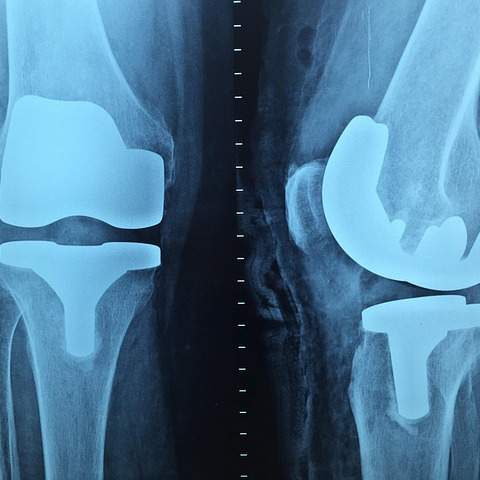

올바른서울병원 정형외과는 최첨단 의료 장비를 통해 정확한 진단과 효과적인 치료를 제공합니다. MRI, CT, X-ray 등 최신 영상 장비를 통해 환자의 상태를 정확하게 파악하고, 개인별 맞춤 치료 계획을 세웁니다.